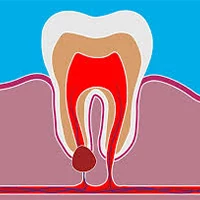

کیست دندان چیست؟

کیست دندان یک حفره غیرطبیعی در استخوان فک است که داخل آن مایع، چرک یا مواد نیمهجامد قرار دارد. این ضایعه معمولاً در اطراف ریشه دندان عفونی یا اطراف دندانهای نهفته تشکیل میشود.

🔹 کیست رادیکولار (پریآپیکال)

شایعترین نوع کیست که در نوک ریشه دندان عفونی ایجاد میشود.